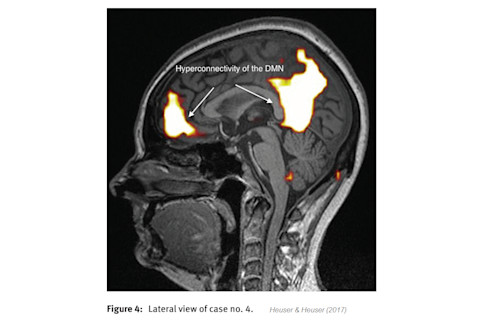

To investigate a possible brain basis of the EHS, the patients had resting state fMRI scanning. Heuser and Heuser say that "all ten patients had abnormal functional MRI brain scans", but I'm not convinced. The images in the paper appear to show the functional connectivity of the default mode network (DMN) for each patient. The images supposedly reveal abnormal activity, but no statistics seems to have been used to verify this - someone has just decided that the blobs are too big:

This looks like a perfectly normal DMN to me. Very few details are given of the fMRI scanning protocol or the data analysis pipeline. In fact, it seems that Heuser and Heuser simply sent their patients to be scanned at a commercial facility (MICSC) and then received a report like this: